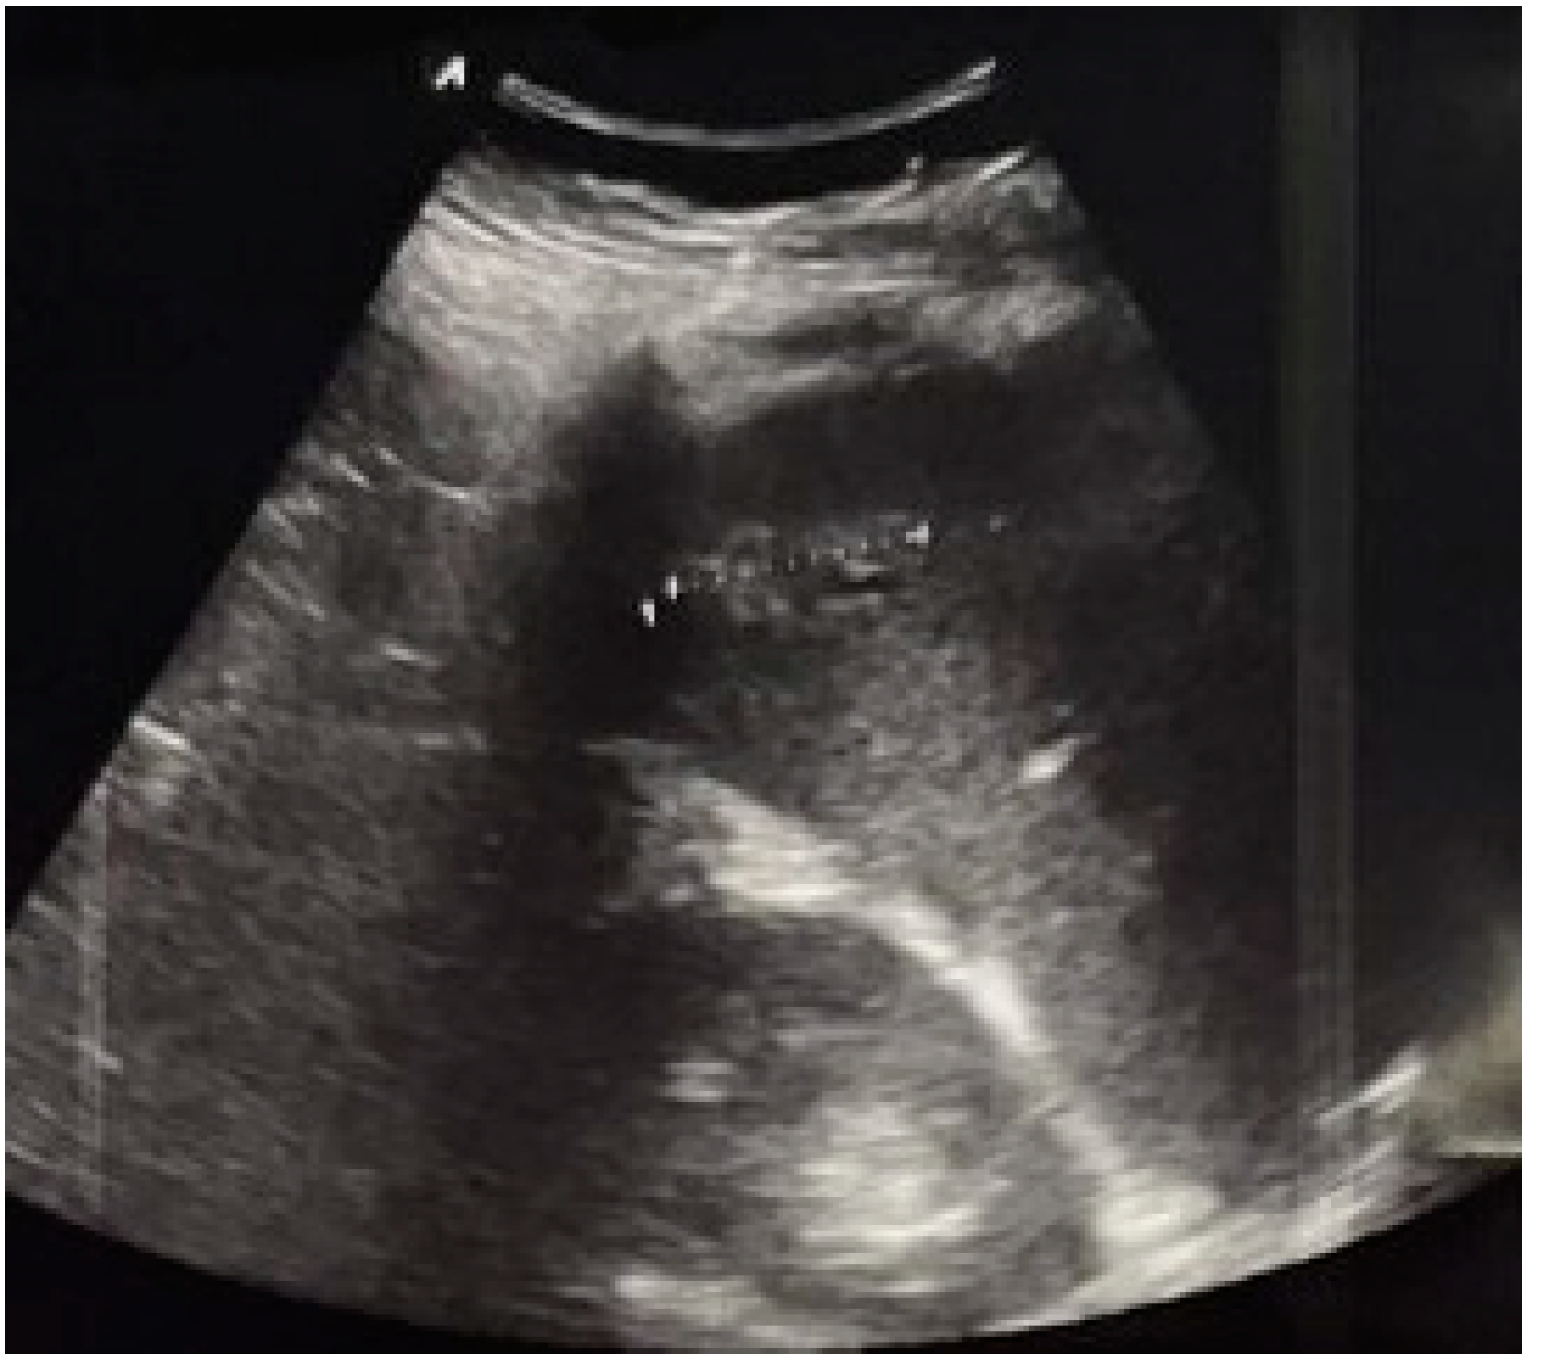

7. Intestinal Obstruction